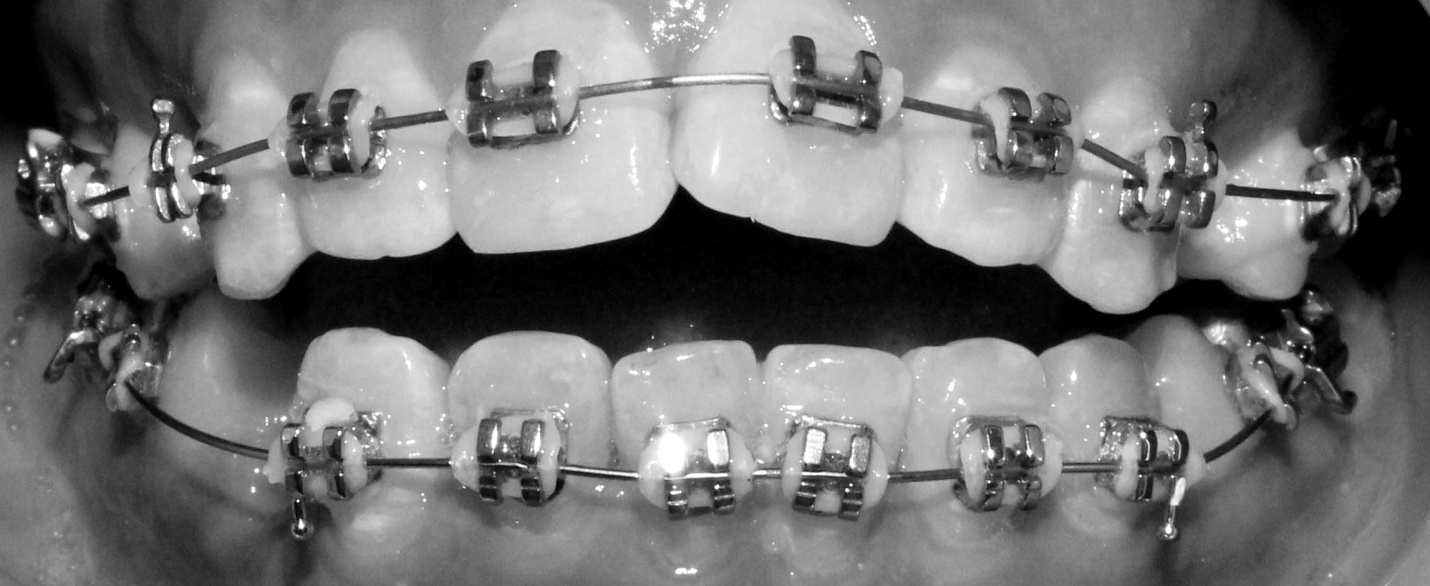

Sau tìm hiểu từ nhiều nguồn, Trang quyết định đến một trung tâm nha khoa. Được bác sĩ ở đây thăm khám, tư vấn, cuối cùng cô quyết định chọn phương pháp niềng răng. Đeo niềng trong nhiều tháng, cũng gặp không ít khó khăn trong chăm sóc răng miệng, nhưng với quyết tâm trở nên đẹp hơn Trang đã kiên trị cho đến ngày tháo niềng.![]() |

| Hàm răng được lắp niềng. |